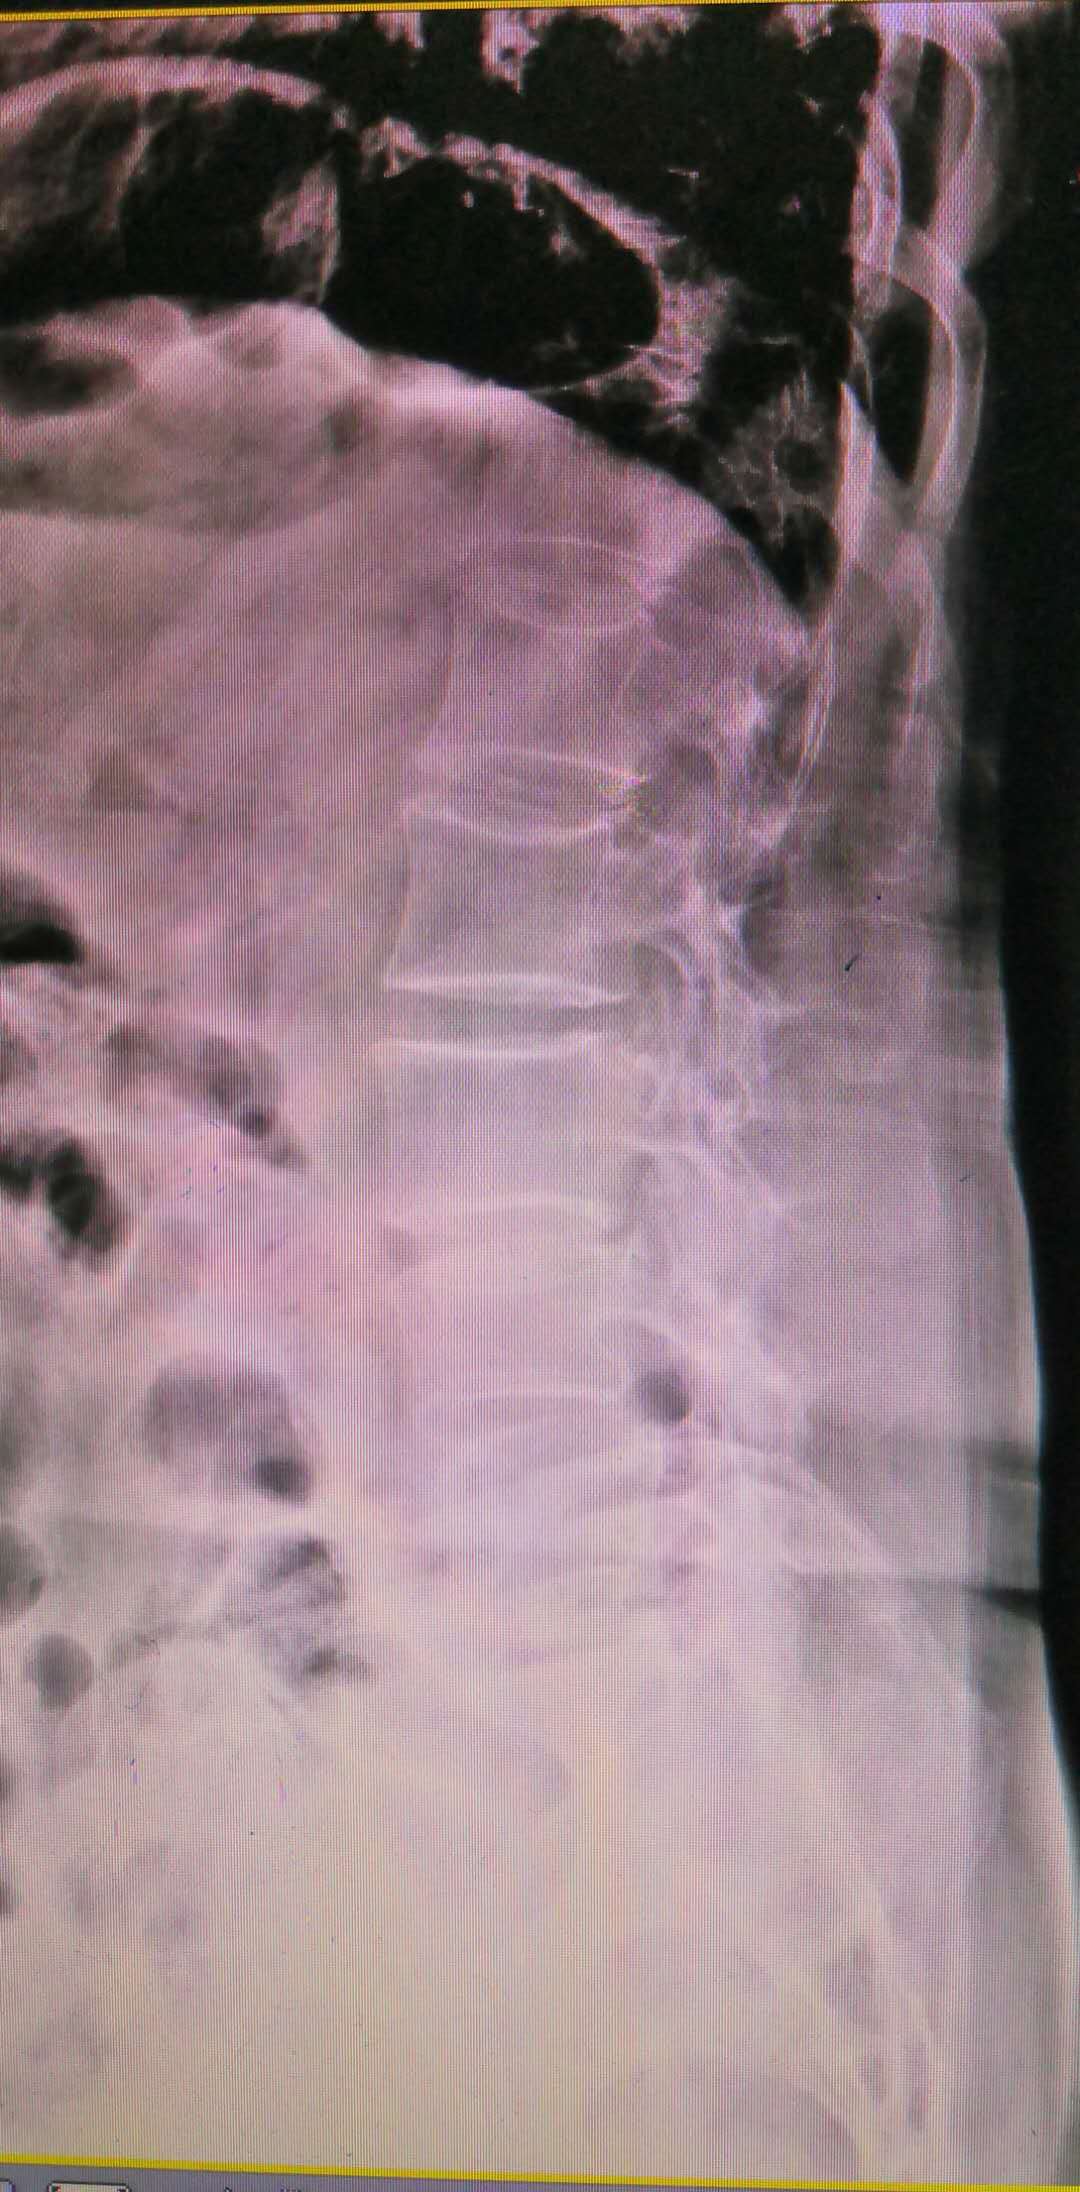

而腰椎不稳的图片完全不一样,如下图所示:

脊柱侧弯,L4椎体前度滑脱